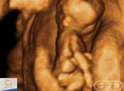

Nota:The fine motor control displayed just ten weeks after fertilization by this little one's right hand is impressive.Roteiro: गर्भाधान के 10 सप्ताह बाद अंगुलियों के अनूठे निशान दखाई देते हैं। इन निशानों को जीवनभर पहचान के लिए उपयोग में लाया जा सकता है। |